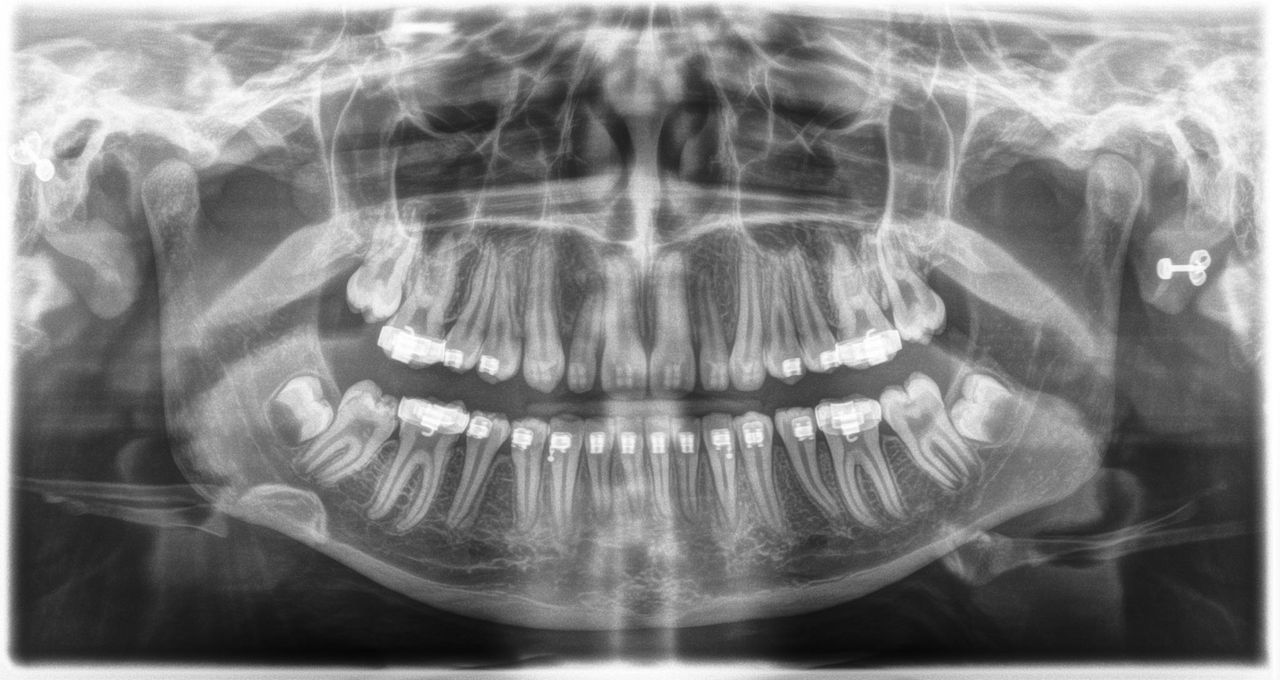

L’unité de radiographie 2D permet de s’immerger facilement dans le monde de l’imagerie numérique. Grâce à la technologie de capteur CsI et à son interface simple, vous bénéficiez de diagnostics fiables à chaque fois. L’option céphalométrique fait également de l’Orthophos E un partenaire fiable pour l’orthodontie. Dotez votre cabinet d’une large gamme de services qui ne sont possibles qu'avec l'imagerie numérique.

Grâce au capteur CsI 2D et à la qualité d’image fiable

Pour les diagnostics de base en 2D